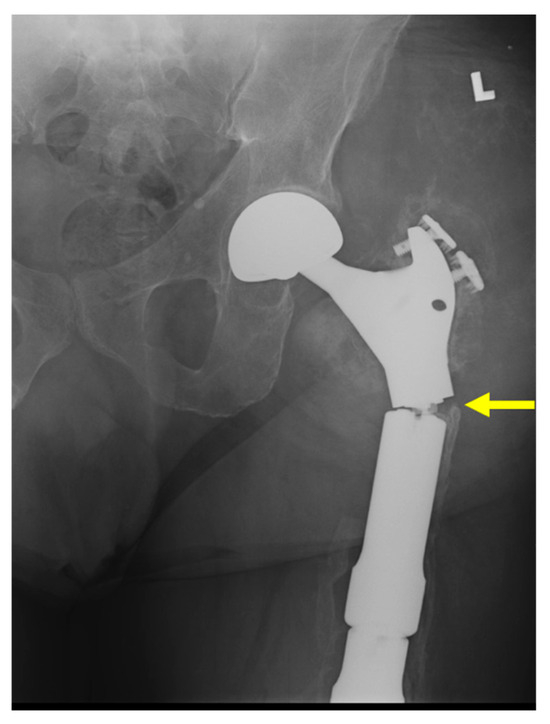

2.2. Type 2 Failures—Loosening and Nonunion

2.2.1. Endoprosthetic Aseptic Loosening

2.3. Type 3 Failures—Structural

2.3.1. Structural Failure of Endoprostheses